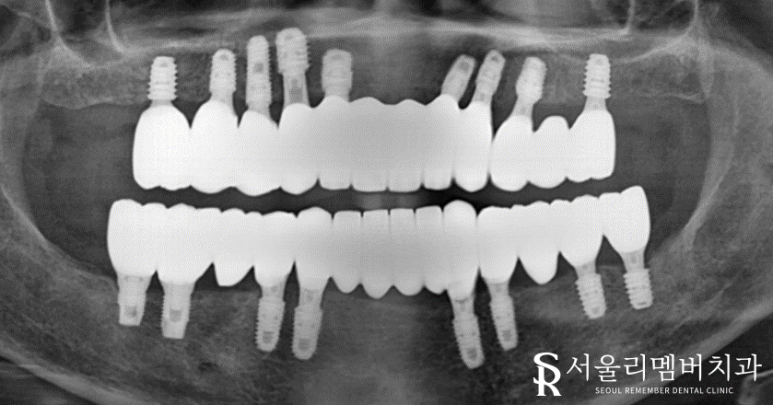

엑스레이를 보면 남아있던 치아 대부분에서 치근단 염증(뿌리)이 진행되고 있었는데요.

조금만 내버려 둬도 곧 자연 발치가 될 것으로 예상되었습니다.

식립 할 개수가 많기 때문에 좀 더 정확한 분석이 필요했는데요.

주변 조직과의 관계, 위치, 형태를 확인한 뒤에 본격적인 치료 진행했습니다.

정확한 위치에 단단하게 심어주었습니다.

구강 상태가 좋지 않았던 거에 비해

다행히 골융합은 그리 나쁜 편이 아니네요.

별문제 없이 임플란트를 심을 수 있었습니다.